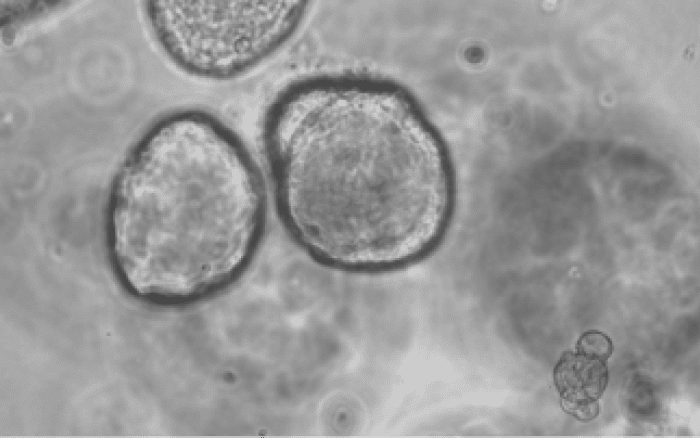

- Model Establishment – Establish normal kidney and ccRCC organoids from fresh surgical specimens

- Genetic Engineering – Generate isogenic aneuploidy organoid models using CRISPRt and other genetic engineering techniques

- Characterisation – Apply multiomics profiling and functional assays to characterise the pro-tumour roles of chromosome 3(p), 9(p) and 14(q) loss